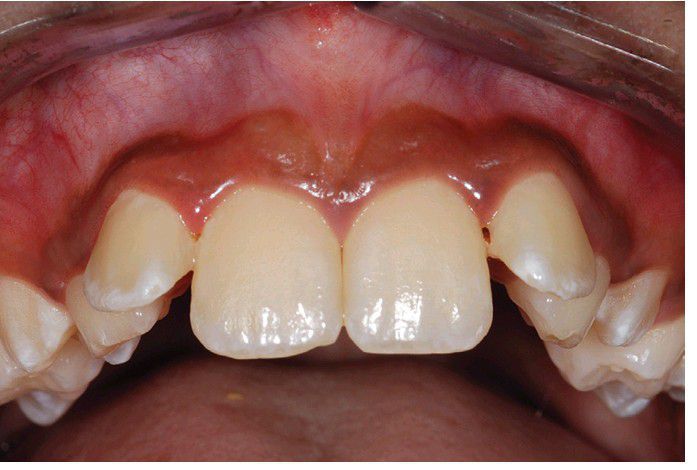

Diffuse pigmentation of the maxillary facial gingiva in a patient with Addison disease.